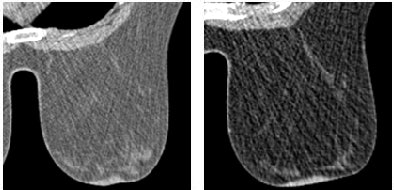

![]()  |

| Fifty-two-year-old woman with invasive ductal carcinoma in left breast. (A and B) Dynamic MDCT images at baseline (A) and one minute (B) after contrast administration depict an irregular lesion with homogeneous enhancement; evaluation of time-attenuation curve showed washout pattern. (C and D) Coronal and sagittal multiplanar reconstructions one minute after contrast administration show lesion in A and B located in upper left quadrant of breast, approximately 2 cm behind nipple. |